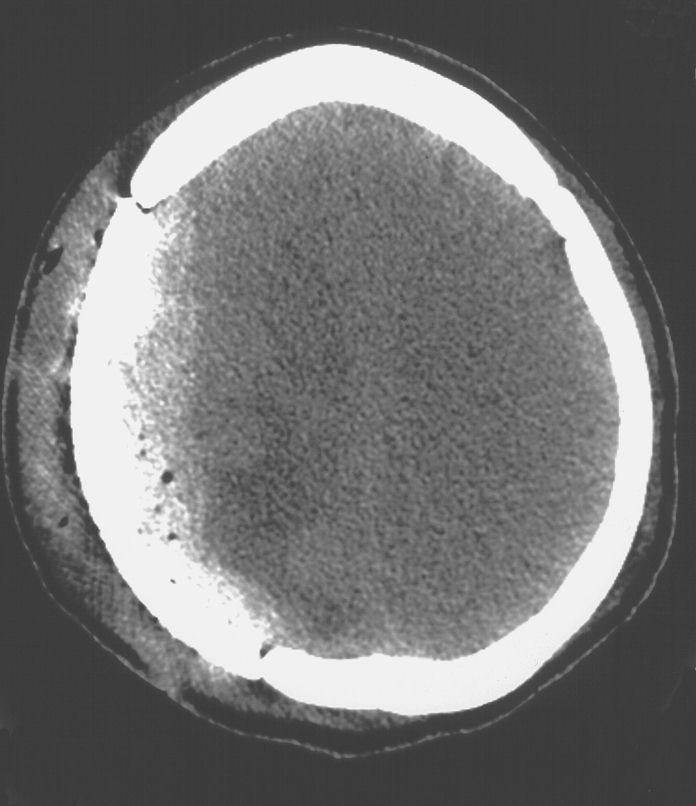

Raccolta ematica extradurale

Per mancanza di sostanza cerebrale o per iniziale anelasticità parenchimale dovuta a mesi d’introflessione cutanea nella breccia, può succedere che la dura non sempre e non prontamente possa essere sospesa fino ad aderire alla superficie interna della protesi. Può così accumularsi del sangue fra dura e manufatto, fin quasi a mimare un ematoma extradurale (Figura 2) con, alle volte, apparente dignità chirurgica.

Di fatto, non si tratta mai di un reale espanso sotto pressione, lo stravaso riempie solo uno spazio ex-vacuo. Non si assiste a compressione parenchimale né a dislocazione della linea mediana.

Un attento monitoraggio neuroradiologico fa rivelare spesso, a distanza di settimane o mesi, la scomparsa della falda ematica ed un’ottimale riespansione parenchimale (Figura 2).

Figura

2. TC encefalica nella seconda giornata post-operatoria.

Modesta falda ematica extradurale di tipo ex-vacuo. RM encefalo a

qualche mese di distanza dall'intervento di cranioplastica.

Completa riespansione parenchimale con scomparsa della falda

ematica sottotecale. |